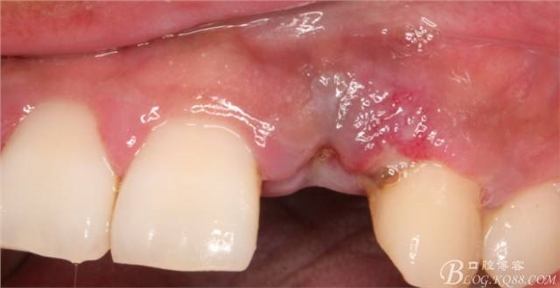

10天拆線一切正常,又過了兩周患者復(fù)診,自述期間無異常??趦?nèi)檢查,真的嚇了一跳,唇側(cè)鼓了個包,擠壓有白色分泌物溢出,絕對不是膿液,液體排除后,術(shù)區(qū)觸診空虛,外觀塌陷。這時候考研大夫的時刻到了,是先觀察一段時間再說?還是馬上進(jìn)行處理?我的回答是:馬上處理!如果你沒有及時處理,而是放患者回家觀察,那么接下來會發(fā)生如下情況:1.回家后患者家屬及親友會有很多你可以想象得到的討論;2.患者及家屬會對你產(chǎn)生不信任,勢必會到其他門診或醫(yī)院檢查,他院大夫會不會發(fā)表對你不利的言論;3甚至?xí)蚁嚓P(guān)法律界人士找你討要說法。